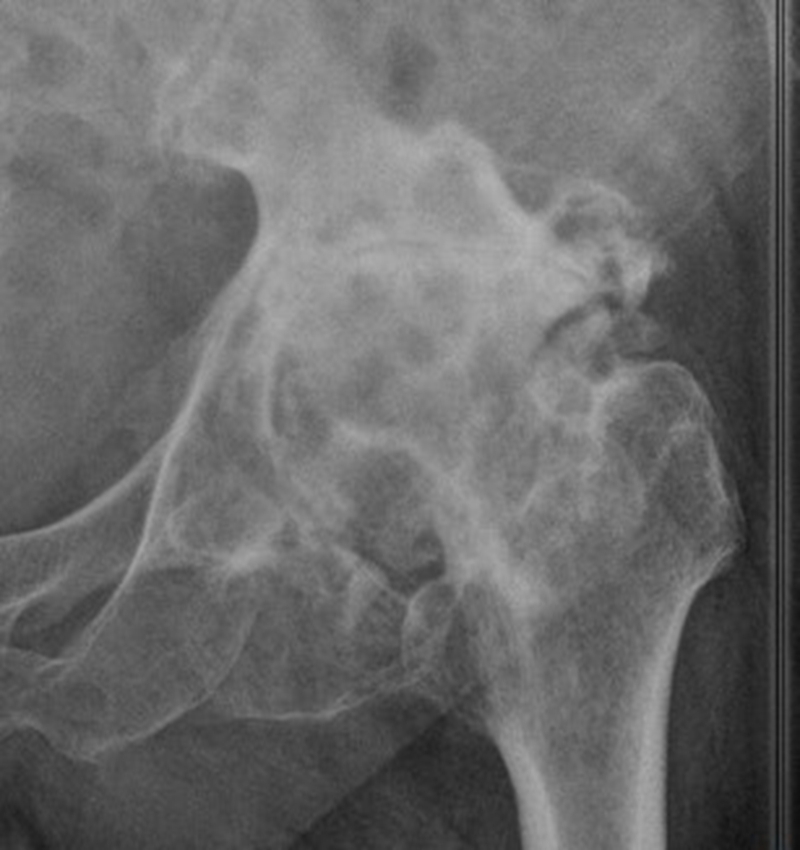

Ⅱ、股骨颈畸形---髋内外翻,offset异常

(1)颈干角偏小(<120°)——髋内翻

髋内翻,颈干角小,偏心距较大,选择high-Offset假体,以维持外展肌张力。

(2)颈干角过大(>140°) ——髋外翻

髋外翻多见于DDH,难度在于股骨距内侧皮质阻挡假体完全坐入髓腔,强行打击造成股骨距骨折。

Ⅲ、干骺端畸形

硬化骨、骨赘、骨质疏松、髓腔宽大

转子间骨折畸形愈合后常导致干骺端畸形,干骺端遗留大量硬化骨或髓腔成角,术中需在确认髓腔开口位置后,首选用小骨刀或高速磨钻去除硬化骨,打通髓腔。

干骺端畸形还可引起髓腔增宽,骨量减少,骨质疏松,不能为近端压配固定型的假体提供良好稳定。宜选用全微孔涂层远端固定假体。